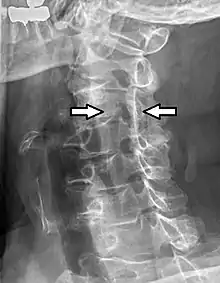

Cervical spinal nerve 4

Projectional radiograph of a man presenting with pain by the nape and left shoulder, showing a stenosis in the intervertebral foramen of cervical spinal nerve 4, corresponding with the affected dermatome.